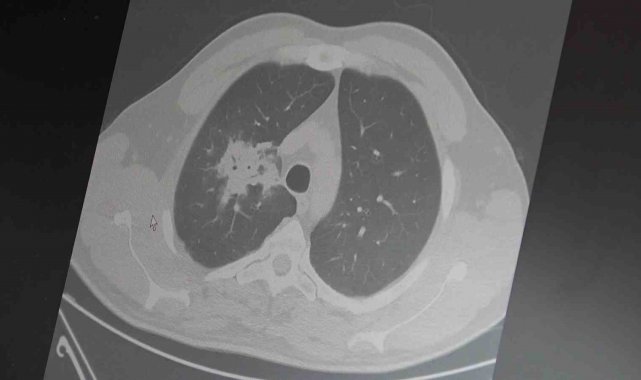

100'den fazla bilimsel çalışmanın incelendiği kapsamlı analizlere dikkat çeken Özkaya, elektronik sigaraların özellikle temas ettiği akciğer ve ağız bölgelerinde kanser riskini artırabileceğine dair güçlü bulgular bulunduğunu belirtti. Uzun vadeli sonuçların henüz tam olarak ortaya çıkmadığını ancak erken uyarı işaretlerinin ciddi olduğunu vurguladı. Araştırmalarda insan, hayvan ve laboratuvar verilerinin birlikte değerlendirildiğini aktaran Özkaya, elektronik sigaraların içerdiği kimyasalların hücre düzeyinde zarara yol açtığının ortaya konulduğunu ifade etti.

Elektronik sigaraların DNA hasarı, oksidatif stres ve kronik iltihaplanma gibi kanser gelişiminde kritik rol oynayan üç temel mekanizmayı tetiklediğini belirten Özkaya, "Bu üç faktörün doğrudan kanser oluşumuna neden olduğunu biliyoruz" şeklinde konuştu.

2024 yılında yayımlanan bir çalışmaya da değinen Özkaya, hem geleneksel sigara hem de elektronik sigara kullanan bireylerde akciğer kanseri riskinin, sadece sigara içenlere göre dört kat daha fazla olduğunun bildirildiğini kaydetti.